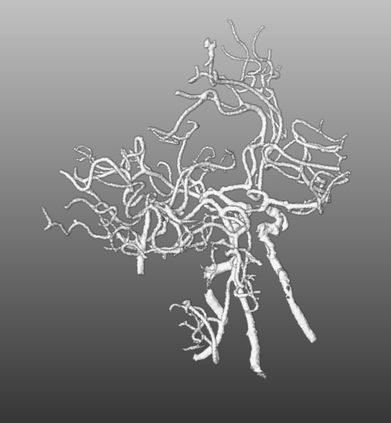

During the diagnosis of ischemic strokes, the Circle of Willis and its surrounding vessels are the arteries of interest. Their visualization in case of an acute stroke is often enabled by Computed Tomography Angiography (CTA). Still, the identification and analysis of the cerebral arteries remain time consuming in such scans due to a large number of peripheral vessels which may disturb the visual impression. In previous work we proposed VirtualDSA++, an algorithm designed to segment and label the cerebrovascular tree on CTA scans. Especially with stroke patients, labeling is a delicate procedure, as in the worst case whole hemispheres may not be present due to impeded perfusion. Hence, we extended the labeling mechanism for the cerebral arteries to identify occluded vessels. In the work at hand, we place the algorithm in a clinical context by evaluating the labeling and occlusion detection on stroke patients, where we have achieved labeling sensitivities comparable to other works between 92\,\% and 95\,\%. To the best of our knowledge, ours is the first work to address labeling and occlusion detection at once, whereby a sensitivity of 67\,\% and a specificity of 81\,\% were obtained for the latter. VirtualDSA++ also automatically segments and models the intracranial system, which we further used in a deep learning driven follow up work. We present the generic concept of iterative systematic search for pathways on all nodes of said model, which enables new interactive features. Exemplary, we derive in detail, firstly, the interactive planning of vascular interventions like the mechanical thrombectomy and secondly, the interactive suppression of vessel structures that are not of interest in diagnosing strokes (like veins). We discuss both features as well as further possibilities emerging from the proposed concept.